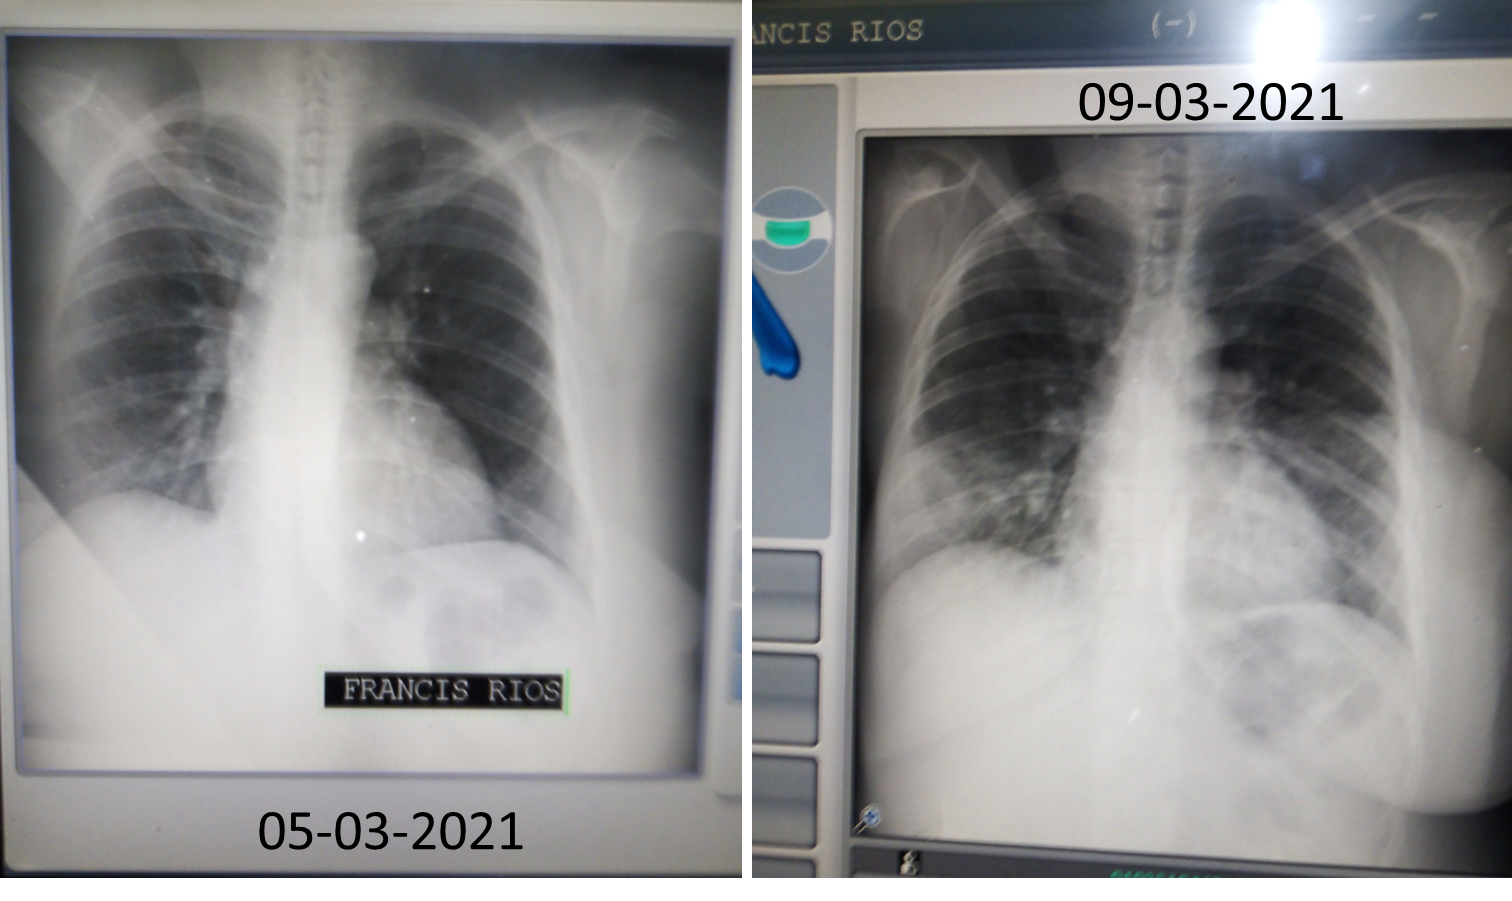

Como el virus seguía aparentemente estable, solo por control, el médico una vez terminada la revisión física, nos dio las órdenes para realizarnos unos nuevos rayos X. Como en el mismo hospital nos podíamos realizar los rayos X, de una vez nos fuimos caminando hasta el Área de Radiología. No podíamos esperar, porque el médico nos dijo que ese mismo día debía comparar los nuevos ralos nuevos rayos X con los anteriores, además de verificar el estado de mi papá, ya que era su primera cita. Para llegar allá, había que caminar un poco, por las patologías de base de mi papá lo llevaron en silla de rueda, mi hermana y yo por supuesto íbamos caminando. Cuando llegamos al área de Radiología, note que yo estaba un poco cansada, finalmente nos tomaron los rayos X, en mi caso, el compromiso pulmonar había avanzado significativamente, tomando en cuenta el corto tiempo.

Como pueden ver en la imagen anterior, en los rayos X del 05 de marzo, solo había unas pocas lesiones pulmonares, en el caso de las del 09 de marzo, casi la mitad de mis dos pulmones estaban comprometidos, se había trasformado en una neumonía bilateral. Cuando nos regresábamos al consultorio para que el médico viera los nuevos rayos X, le dije a mi hermana que siguiera con mi papá, que yo iba a caminar más lento, porque me sentía un poco cansada. Mientras caminaba de regreso, empecé a sentirme cada vez peor, comencé a ver borroso, me costaba respirar y el cansancio casi no me dejaba caminar. Como pude, logre llegar al estacionamiento frente a SATRAMO, ya mi hermana estaba allí y al verme dando traspiés corrió a alcanzarme, mientras le gritaba al médico, que corriera, que yo estaba colapsando.

El médico al comparar los rayos X y revisar los síntomas, nos explicó que, la agresividad del virus indicaban inequívocamente, que el virus que habíamos contraído era la variante Brasilera de Covid-19. Por alguna razón, en mi caso a diferencia del resto de mis familiares, mi organismo no estaba respondiendo adecuadamente al tratamiento oral, por lo que había que cambiarlo a intravenoso. Además por el colapso que acababa de sufrir, necesitaba que me suministraran permanentemente oxígeno, porque estaba en riesgo de sufrir un trombo pulmonar y por ende muerte súbita. Así inicio una nueva etapa de la pesadilla, pero como la historia ya está muy larga, por ahora la dejaré hasta aquí y próximamente les contaré como transcurrieron esos siguientes 19 días de hospitalización y mi posterior recuperación.